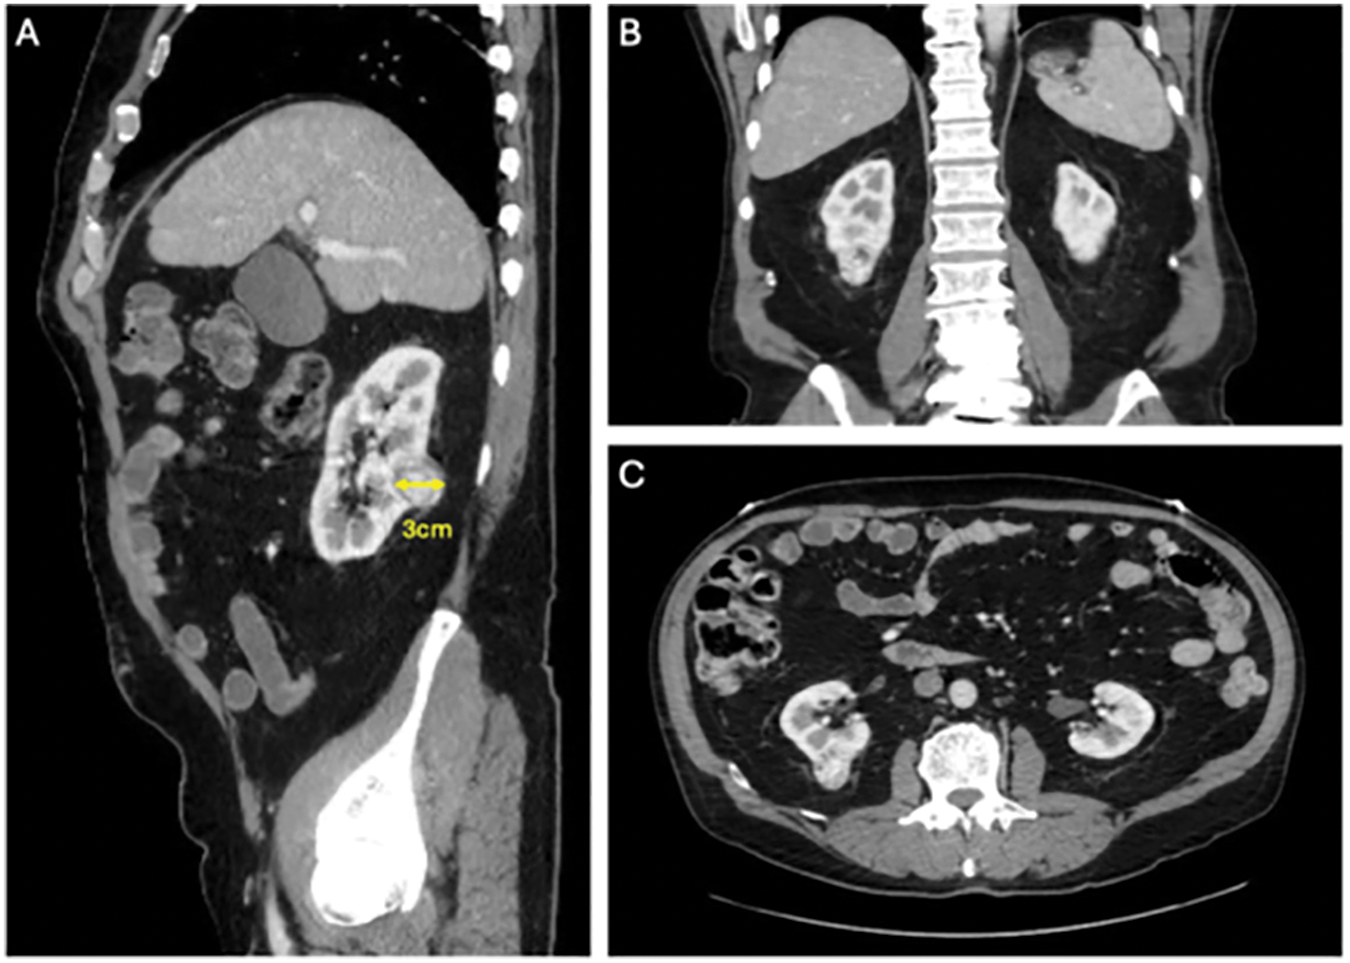

The nature of this “How I Do It” article was IRB exempt. Informed consent was not obtained as no patient identifiable information was included within our manuscript. Index patient number 1 is a 66-year-old man with a body mass index (BMI) of 27.8 kg/m2 who was found to have an enhancing, exophytic, 3 cm right posterior lower pole renal mass. Cross-sectional imaging is shown in Figure 1. Nephrometry score was 4P. The patient underwent a successful right SP PN via an RP approach. Total operative time was 147 min, warm ischemia time was 25 min, estimated blood loss was 200 mL, and estimated glomerular filtration rate (eGFR) immediately post-operatively remained stable at 75 mL/min/1.73 m2. The patient was discharged the same day without narcotics and did not have any 30-day complications. Final pathology demonstrated pT1aNx clear cell renal cell carcinoma with negative surgical margins. Additionally, we present a total of five patients in Table 1 who underwent SP PN via an RP approach to highlight a case series.

FIGURE 1. Abdomen computed tomography (CT) demonstrating a 3 cm exophytic, posterior, right lower pole renal mass